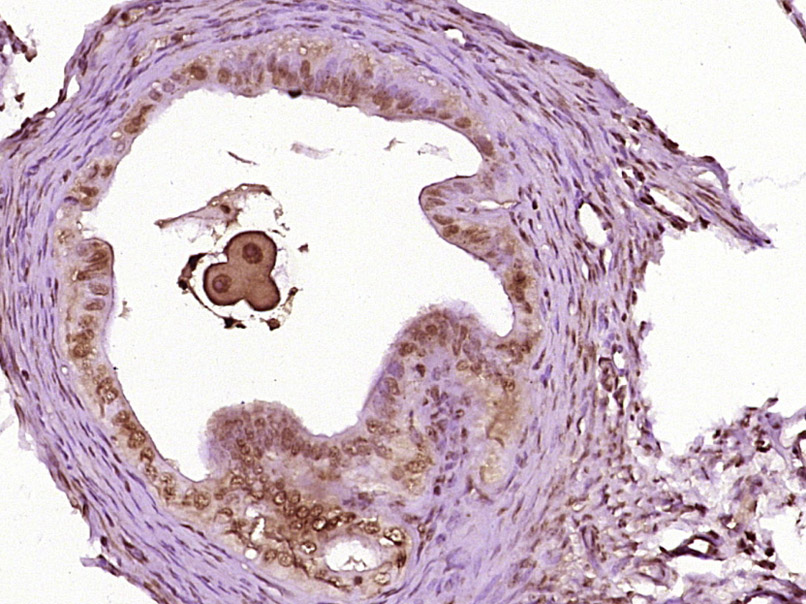

Tissue/cell: mouse embryo tissue; 4% Paraformaldehyde-fixed and paraffin-embedded; Antigen retrieval: citrate buffer ( 0.01M, pH 6.0 ), Boiling bathing for 15min; Block endogenous peroxidase by 3% Hydrogen peroxide for 30min; Blocking buffer (normal goat serum,C-0005) at 37℃ for 20 min; Incubation: Anti-Nanog Polyclonal Antibody, Unconjugated(bs-10414R) 1:200, overnight at 4°C, followed by conjugation to the secondary antibody(SP-0023) and DAB(C-0010) staining

Tissue/cell: rat testis tissue; 4% Paraformaldehyde-fixed and paraffin-embedded; Antigen retrieval: citrate buffer ( 0.01M, pH 6.0 ), Boiling bathing for 15min; Block endogenous peroxidase by 3% Hydrogen peroxide for 30min; Blocking buffer (normal goat serum,C-0005) at 37℃ for 20 min; Incubation: Anti-Nanog Polyclonal Antibody, Unconjugated(bs-10414R) 1:200, overnight at 4°C, followed by conjugation to the secondary antibody(SP-0023) and DAB(C-0010) staining